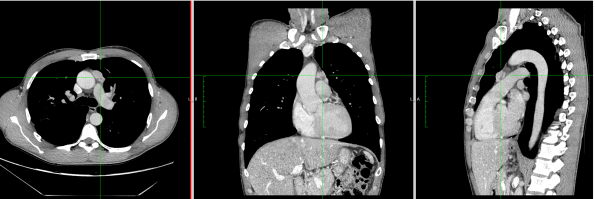

1. CT-Scan and PET-Scan

A 47-year-old male patient with no previous medical history was referred to the institution with a diagnosis of mediastinal mass suspected of being thymoma, without any clinical or laboratory signs of myasthenia gravis. The chest CT-scan showed a 2.5 cm lesion with no clear signs of infiltration of surrounding tissues and with a PET uptake of SUV max 4. The patient was scheduled for subxiphoid bilateral robotic-assisted thymectomy.